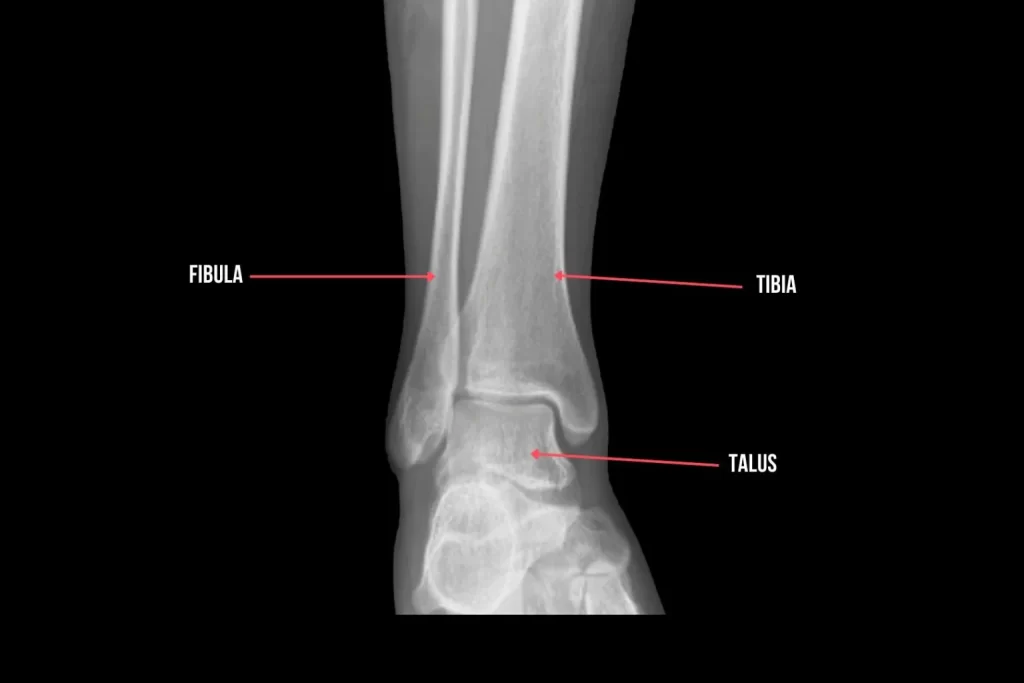

Ankle